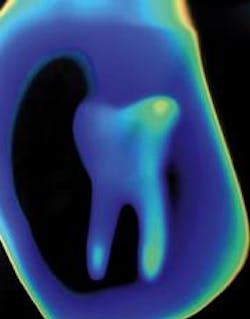

Dental radiographs are a tool for the diagnosis of decay or disease. Patients present with individualized needs; their radiographic needs should be just as individualized. Any radiograph exposed should benefit patient care. Every patient does not need the same protocol. Thorough clinical evaluation should be instituted prior to exposing the patient to radiation. Practitioners should make a viable effort to obtain previous radiographs from former dentists prior to exposing patients. Even "historical" radiographs will render information concerning the patient.

The guidelines have their framework in posterior interproximal radiographs. With these, the detection of interproximal caries and some levels of periodontal disease may be achieved. Certain clinical findings listed indicate when the dental radiographs will prove useful in diagnosis of the patient's current dental state. The guidelines do allow for radiographs to be taken on pregnant patients "as abdominal exposure during dental radiography is negligible." Again, clinical judgment and prudent selection are essential.